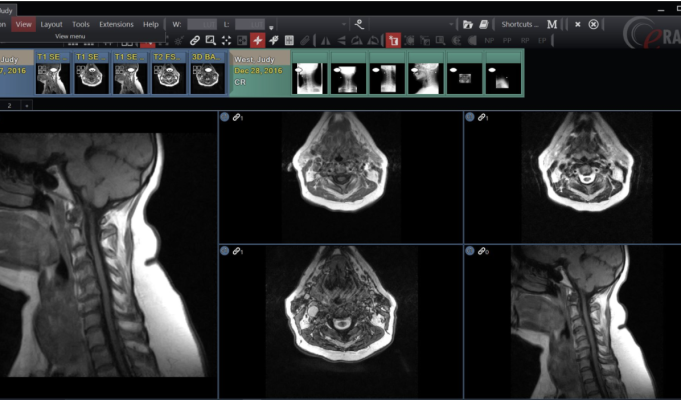

Портфолио DeepHealth основано на сильных сторонах систем управления радиологической информацией и изображениями eRAD , искусственного интеллекта легких Aidence и искусственного интеллекта простаты Quantib , которые теперь переименованы и являются частью DeepHealth.